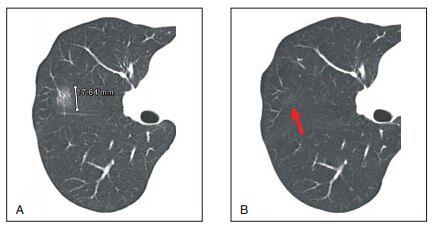

▲图2 患者男性,47岁。良性纯 GGO 结节。A.薄层CT扫描显示右上肺叶一个7 mm的纯结节GGO;B.薄层CT显示病变6个月后不减少或不消失。病理检查示局灶性肺间质纤维化